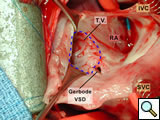

Figure 8 shows the view of the open right atrium taken from the head of the table. The superior vena cava (SVC) and inferior vena cava (IVC) are identified. There is a catheter tip in the mid-portion of the right atrium. The tricuspid valve has been outlined with a dotted blue line. The Gerbode ventriculo-atrial defect is indicated.

In Figure 9, a 4-mm probe is being shown passed across the ventriculo-atrial defect.